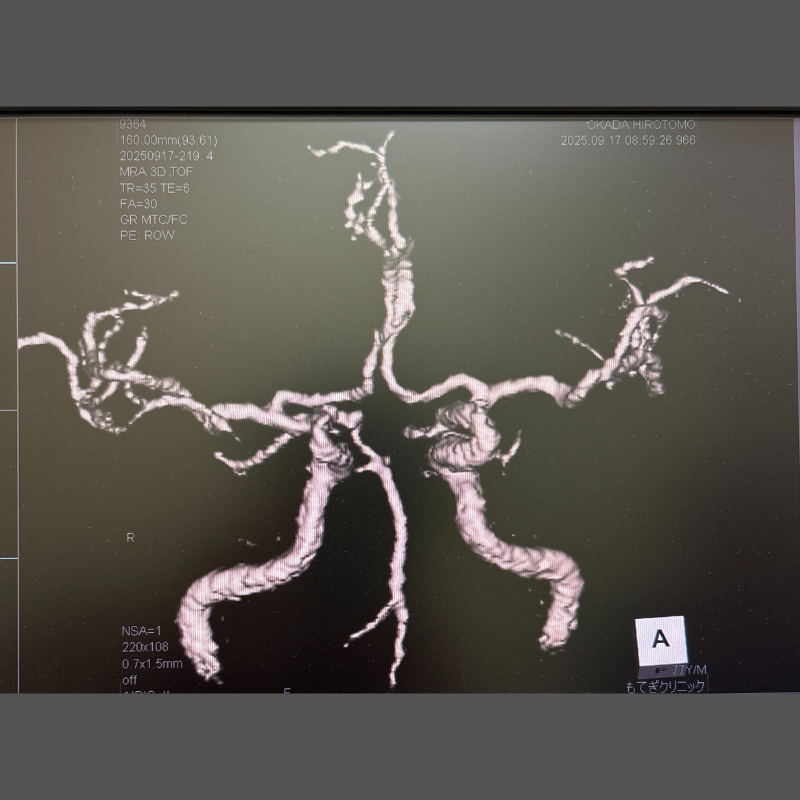

MRI画像例

下の画像は、当院で行うMRI・MRA検査で撮影できる脳の写真の一例です。

MRIでは脳の形や組織の状態を、MRAでは脳の血管の様子を詳しく確認できます。

当院では、CTやMRIで撮影した2D画像(平面画像)を3D画像(立体画像)に変換して表示できます。

立体的に確認することで、血管の通り道や狭くなっている部分、脳動脈瘤などの形をより詳しく観察することができます。

3D画像